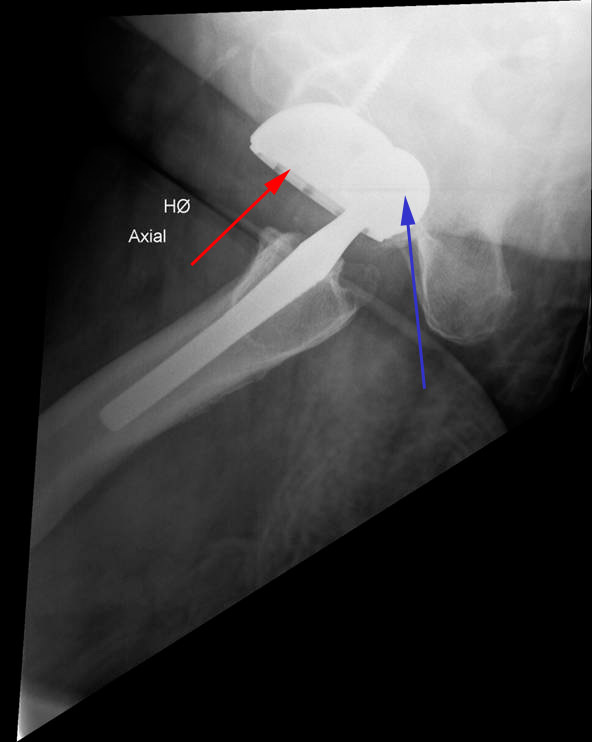

Hofte, proteseluksation, røntgen

Patient med fuld hofteprotese. Røntgenbilledet viser, at protesen er gået af led. Det kunstige ledhoved (blå pil) er gledet bagud af den kunstige hofteskål (rød pil).